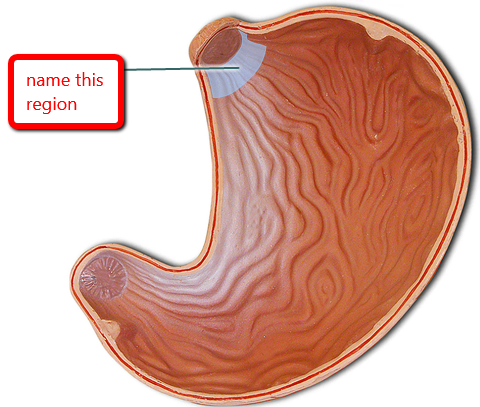

Cardia (of stomach)

Fundus (of stomach)

Body (of stomach)

Gastroesophageal sphincter

Pyloric Sphincter

Pylorus (of stomach)

Rugae (of stomach)